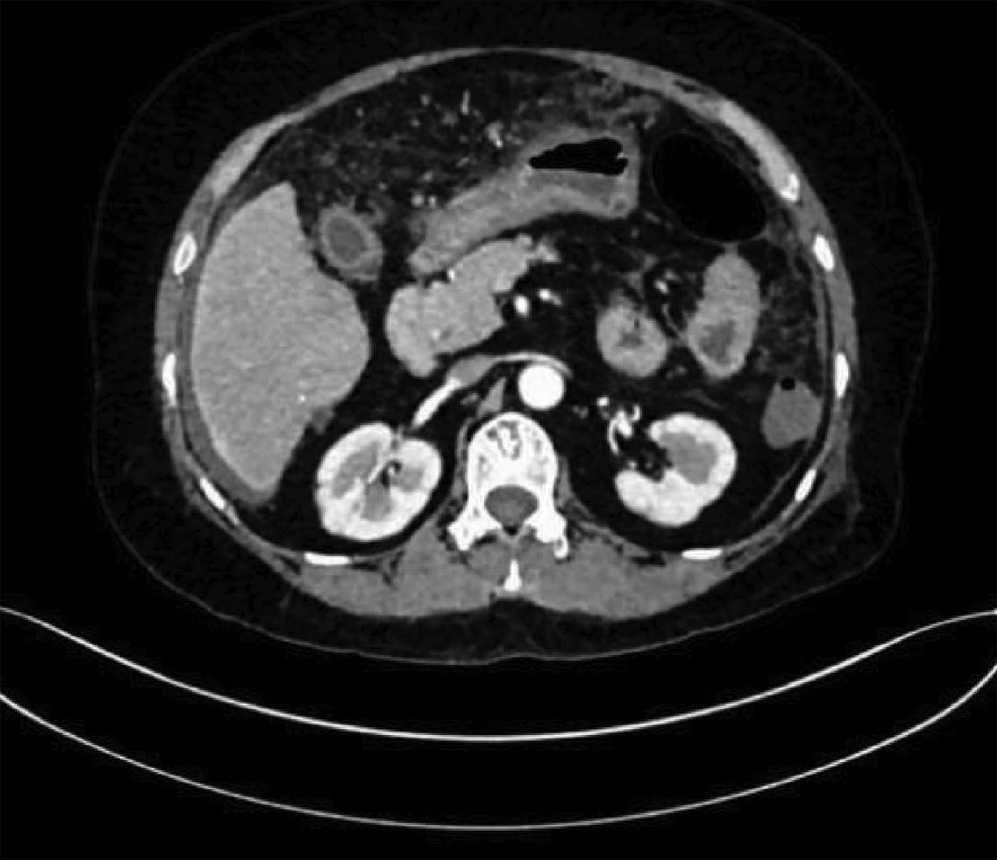

IgG4-related retroperitoneal fibrosis: A case report

Zhaoxia LI, Yang LIU, Nan LI, Zhuhui JI, Guijie XIN

2022, 38(5): 1126-1128. DOI: 10.3969/j.issn.1001-5256.2022.05.030

Abstract(758) HTML (364) PDF (2161KB)(55)

Abstract: